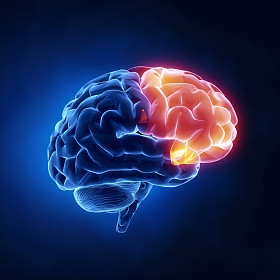

图司机为设计师提供高清磁共振脑: 显示大脑右顶叶脑肿瘤图片版权下载,图片为科学技术,大小为4.35MB,尺寸为3407 x 3407px,更多关于图像,蓝色,背景,隔离,リボンとユーロ,人类,人,健康,头,医学,保健服务,医疗,文家,黑色,猫,博士,医院,病人,治疗,疾病,显示,癌症,电影,雷,权利,生病,在,头骨,大众,为,的,诊断,解剖,大腦,x 光,手术,扫描,放射学,X 射线,颅骨,神经病学,肿瘤,叶,磁共振成像,大脑,麻痹,ct,神经外科,顶叶,神经,癌,转移,脑波机商用高清版权图片,快来图司机免费下载吧。